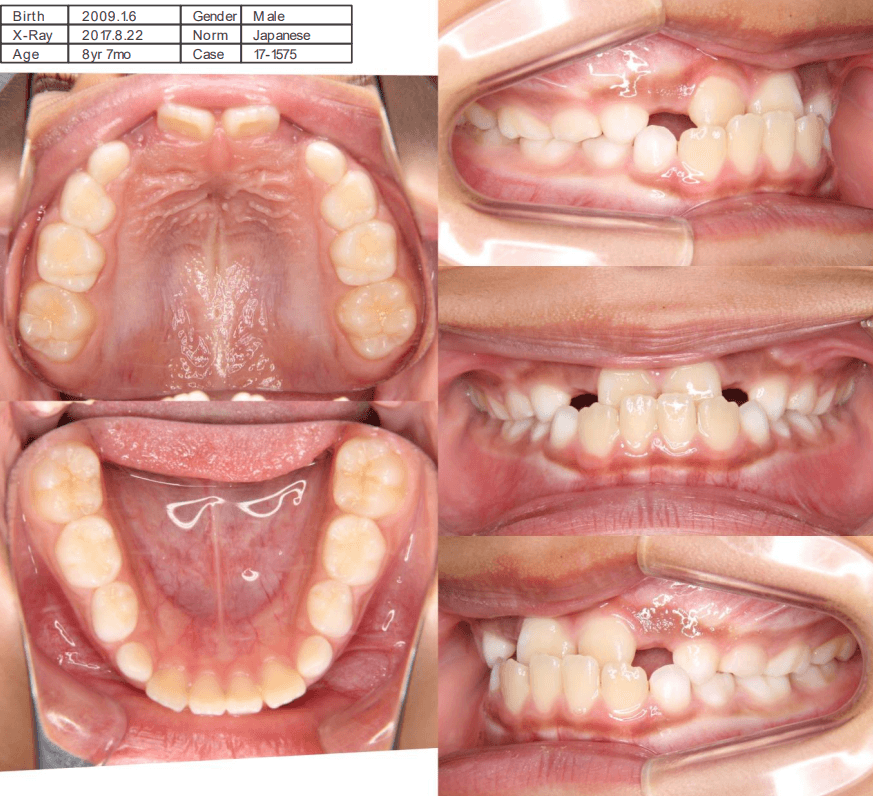

| 年齢・性別 | 7歳8ヶ月の男児 |

|---|---|

| 主訴 | 前歯の噛み合わせが逆で、見た目や食事に違和感があることを心配されて来院されました。 |

| 治療期間・回数 | 3年6ヶ月 |

| 費用 | 430,000円(税別) |